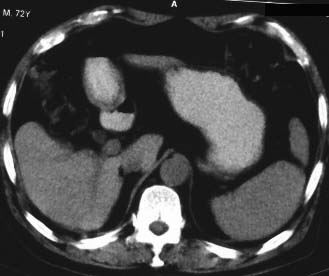

男 56 腹部不舒

典型肝硬化:1、肝各叶大小的比例失常;2、肝表面明显凹凸不整,边缘变钝;3、肝实质密度一般与正常肝无明显改变;4、肝裂增宽;5、门静脉增宽,脾静脉扩张扭曲;6、脾脏虽然不大,但不是所以肝硬化的脾脏都增大。

典型肝硬化:1、肝各叶大小的比例失常;2、肝表面明显凹凸不整,边缘变钝;3、肝实质密度一般与正常肝无明显改变,但肝右叶似可见再生结节影;4、肝裂增宽;5、门静脉增宽,脾静脉扩张扭曲;6、脾脏增大. 脾脏大小的标准有:1脾脏的左右径(大于5个肋单元) 2脾脏的宽度 3脾脏的上下径(超过肝下缘) 请参考.

典型肝硬化:1、肝各叶大小的比例失常;2、肝表面明显凹凸不整,边缘变钝;3、肝实质密度一般与正常肝无明显改变,但肝右叶似可见再生结节影;4、肝裂增宽;5、门静脉增宽,脾静脉扩张扭曲;6、脾脏增大.

典型肝硬化:1、肝各叶大小的比例失常;2、肝表面明显凹凸不整,边缘变钝;3、肝实质密度一般与正常肝无明显改变,但肉眼观察与脾胀密度低或等密度;4、肝裂增宽;5、门静脉增宽,脾静脉扩张扭曲;6、脾脏增大.

典型肝硬化:1、肝各叶大小的比例失常;2、肝表面明显凹凸不整,边缘变钝;3、肝实质密度一般与正常肝无明显改变,4、肝裂增宽;5、门静脉增宽,脾静脉扩张扭曲;6、脾脏增大.

肝硬化表现符合,肝脾ct值有倒置,考虑局灶性肝脂肪浸润